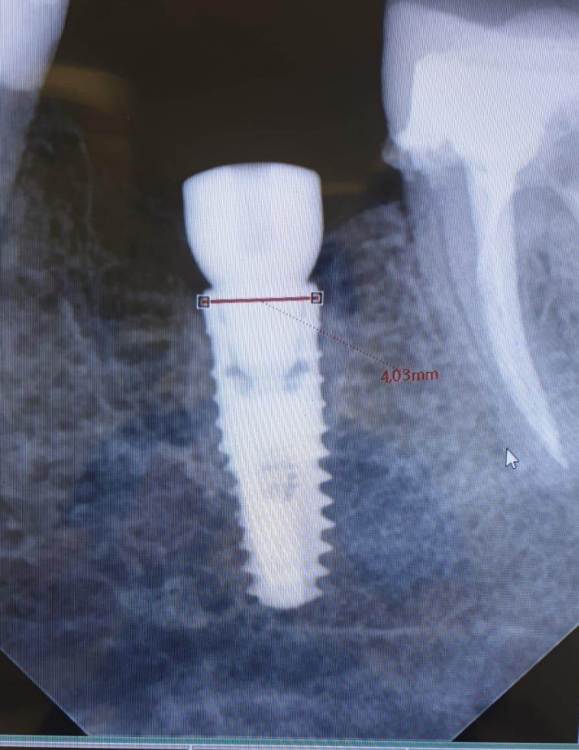

АнтонТЛТ Опубликовано 30 июля, 2021 Поделиться Опубликовано 30 июля, 2021 Xive это, только формирователь не от него 1 Ссылка на комментарий

Irouil Опубликовано 31 июля, 2021 Поделиться Опубликовано 31 июля, 2021 Xive с конусом? И где полированная фаска? Ссылка на комментарий

АнтонТЛТ Опубликовано 31 июля, 2021 Поделиться Опубликовано 31 июля, 2021 1 час назад, Irouil сказал: Xive с конусом? И где полированная фаска? Без конуса, то что конусный фдм туда прикрутили, не значит, что сам интерфейс имплантата конусный) Фаска выше линии замера 2 Ссылка на комментарий